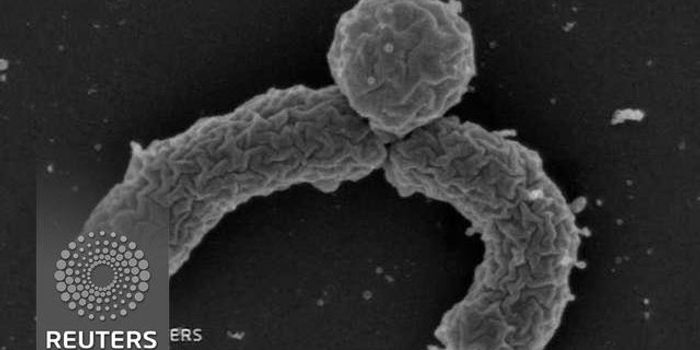

JAN 08, 2018VideosEscherichia coli is a bacterium that normally lives in the gastrointestinal tract, and when it ends up somewhere else, i ...